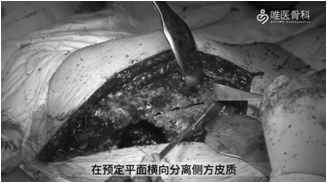

②用摆锯按照截骨线锯开股骨后方皮质,在预定平面横向分离侧方皮质。用骨刀穿透前侧皮质,并将截骨块向前方掀开,直视下清除残留骨水泥。